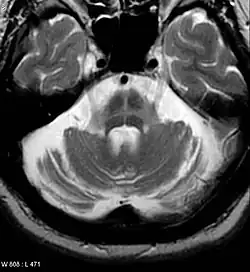

Both MRI and CT scanning may show a decrease in the size of the cerebellum and pons in those with cerebellar features (MSA-C). The putamen is hypointense on T2-weighted MRI and may show an increased deposition of iron in the Parkinsonian (MSA-P) form. In MSA-C, a "hot cross bun" sign is sometimes found; it reflects atrophy of the pontocerebellar tracts that give T2 hyper intense signal intensity in the atrophic pons.

MRI changes are not required to diagnose the disease as these features are often absent, especially early in the course of the disease. Additionally, the changes can be quite subtle and are usually missed by examiners who are not experienced with MSA.